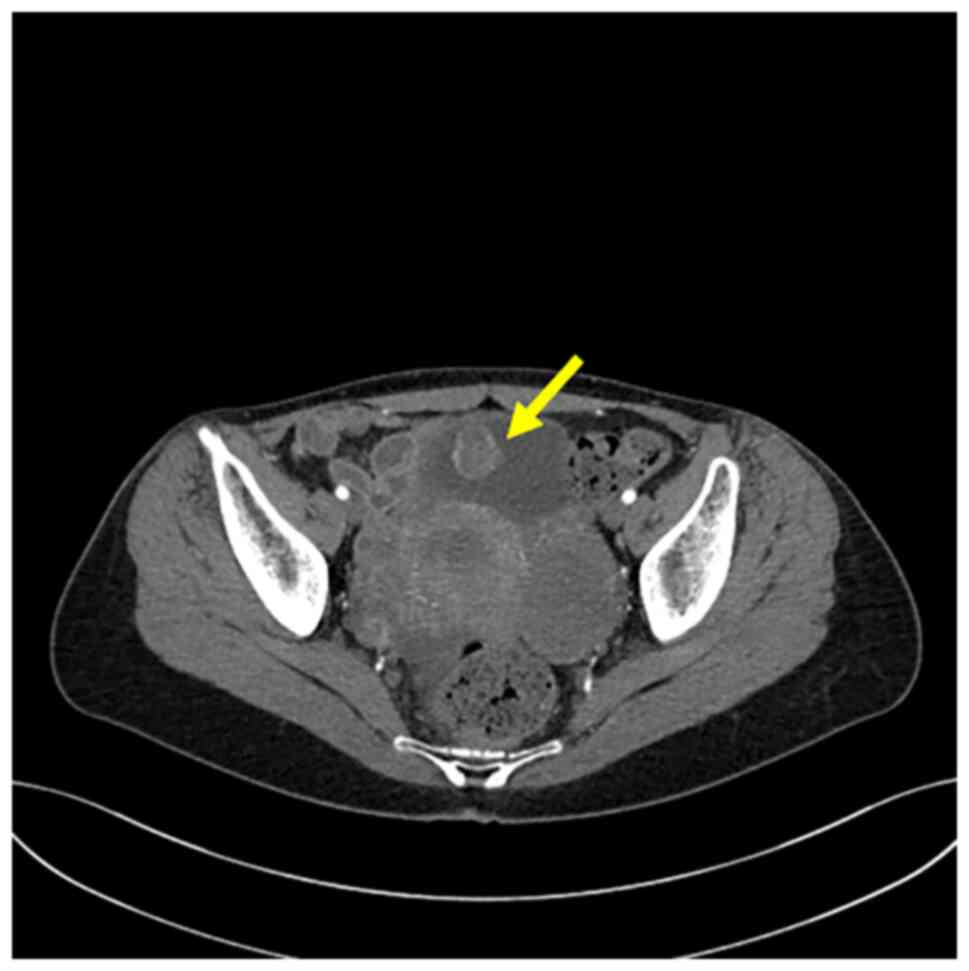

Inflammatory myofibroblastic tumor of the urinary bladder with FN1‑ALK gene fusion: A case report

Inflammatory myofibroblastic tumors (IMTs), which are rare tumors, exhibit myofibroblastic differentiation, often with anaplastic lymphoma kinase (ALK) gene rearrangements. A subset of IMTs identified in the urinary tract have been shown to harbor a fibronectin 1 (FN1)‑ALK gene fusion. In this case report, a case of an IMT with FN1‑ALK fusion in the urinary bladder was presented, and its clinicopathological characteristics were reviewed. A 45‑year‑old female was referred to Chungbuk National University Hospital with gross hematuria. Cystoscopy revealed a solid mass in the bladder. The patient subsequently underwent transurethral resection of the lesion. The mass comprised stellate and spindled myofibroblastic cells that were arranged in loose fascicles, with a myxoid background and a mixed inflammatory infiltrate. Immunohistochemical analysis revealed that the tumor cells were positive for vimentin, cytokeratin AE1/AE3 and ALK, and focal‑positive for desmin. Targeted next‑generation sequencing was subsequently employed to identify the FN1‑ALK fusion. To date, the patient has undergone outpatient follow‑up for 18 months, with no signs of tumor recurrence. To conclude, in total, FN1 has been identified as an ALK fusion partner almost exclusively in cases of genitourinary IMTs [13 bladder IMTs (including the present case) and two uterine IMTs]. In the present case, the FN1‑ALK fusion was found to involve ALK exon 19 and FN1 exon 23. By contrast, the majority of the other IMTs with an ALK fusion have involved ALK exon 20, whereas ALK fusion involving ALK exon 18 or 19 has been reported only in genitourinary IMTs. Therefore, the FN1‑ALK fusion involving ALK exon 18 or 19 may be specific to a subset of IMTs arising in the urinary bladder.